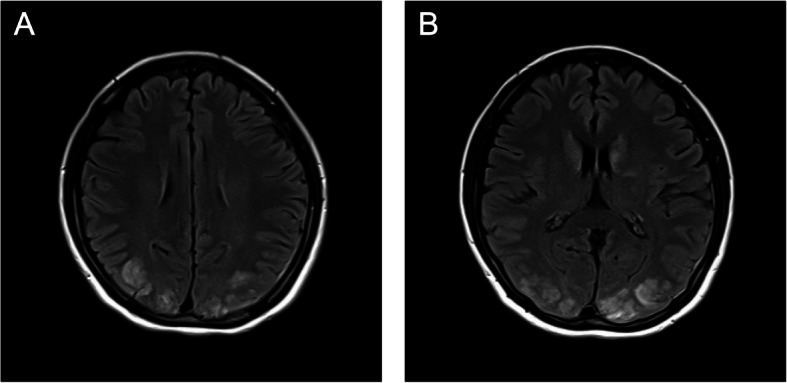

Case presentation: A 29-year-old primigravida developed sustained hypertension during labor. Immediately postpartum, she experienced visual disturbances, followed by altered consciousness and lip-smacking movements. She subsequently developed profound but transient retrograde amnesia, including loss of autobiographical memory. Brain magnetic resonance imaging (MRI) revealed characteristic findings of PRES in the bilateral parieto-occipital lobes, leading to a diagnosis of PRES secondary to preeclampsia.